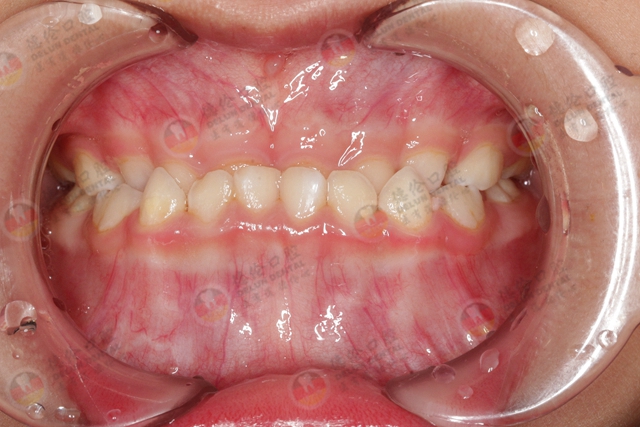

地包天:下牙包住上牙,下巴前伸,呈凹面型。通过矫正之后,下巴回到正常位置,脸型更接近直面型,侧脸和嘴唇形态会更好看

牙性的凸出:矫正后会让牙齿内收,嘴唇也往内收,鼻子会显得凸一些,侧面的轮廓线会更流畅立体。

深覆合:上牙盖住下牙太多,面下1/3很短,脸型偏方,矫正之后下巴会得到一定程度的延伸,侧面也会更流畅。